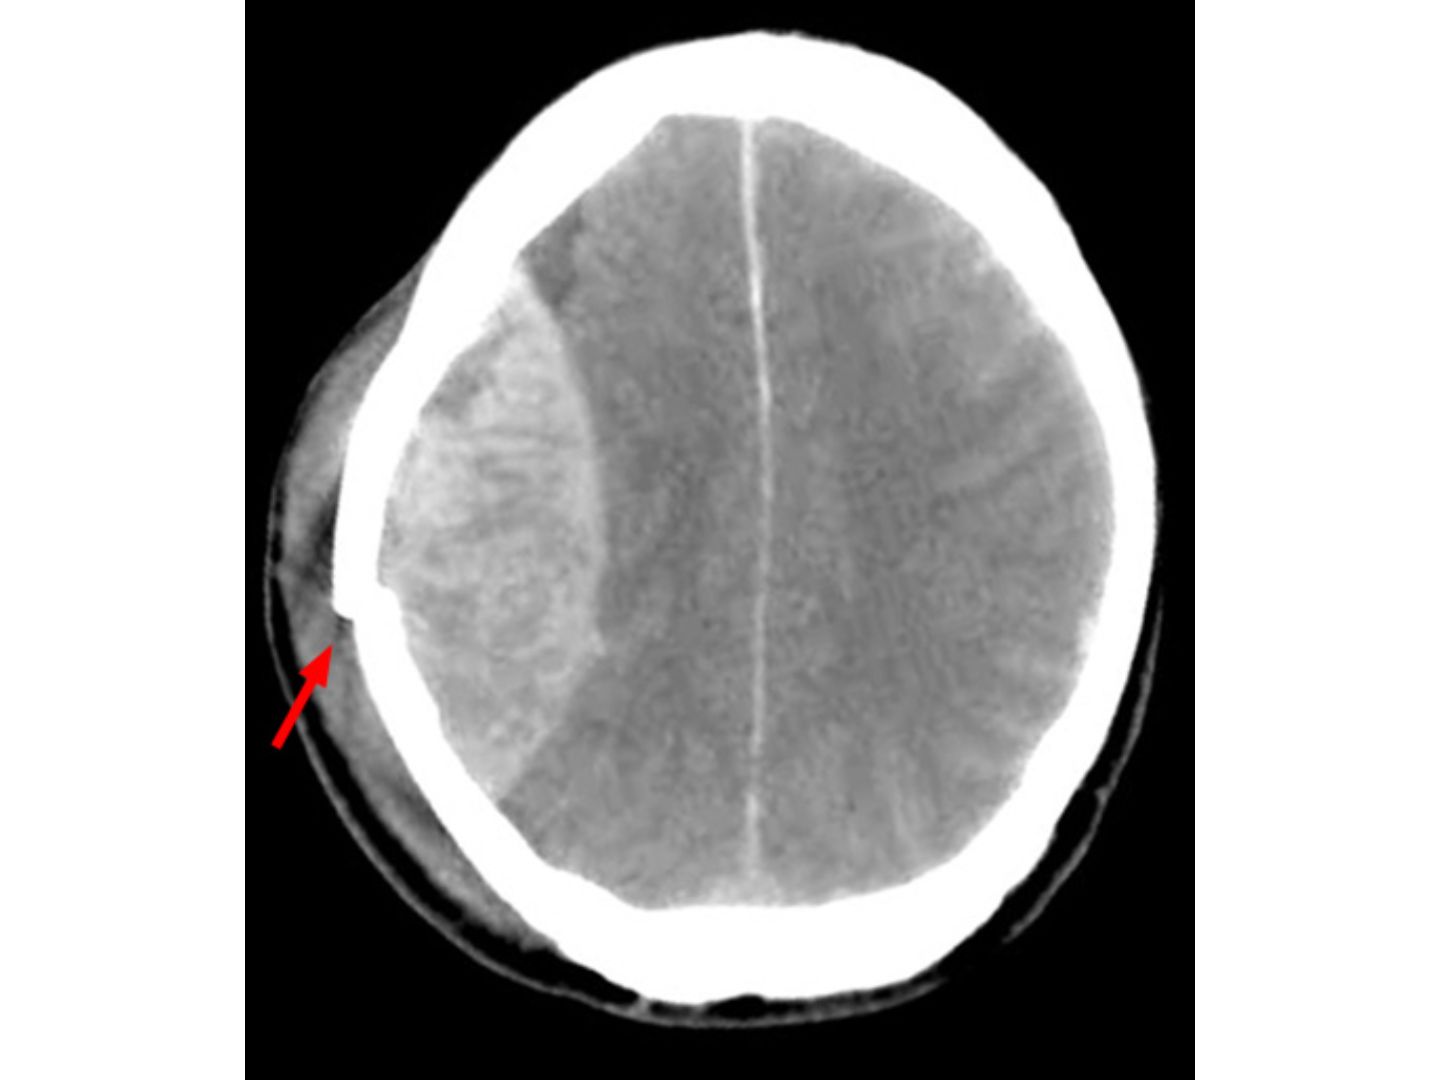

Computertomografische Aufnahme (CCT) des Schädels mit bikonvexer (linsenförmiger) hyperdensen Blutansammlung zwischen Schädelknochen und Dura mater typisch für ein epidurales Hämatom. Der Pfeil markiert die Frakturlinie der Schädelkalotte, welche die Blutung verursacht hat.

CCT: Epidurales Hämatom - Computertomografische Aufnahme (CCT) des Schädels mit bikonvexer (linsenförmiger) hyperdensen Blutansammlung zwischen Schädelknochen und Dura mater typisch für ein epidurales Hämatom. Der Pfeil markiert die Frakturlinie der Schädelkalotte, welche die Blutung verursacht hat.

Hellerhoff. (2009, 1. November). Epidurales Hämatom bei Fraktur (Pfeil) der Schädelkalotte, bikonvexe Form (linsenförmig), computertomografische Aufnahme (CCT). Wikimedia Commons. https://commons.wikimedia.org/wiki/File:Epidurales_Haematom.jpg

CC BY-SA 3.0